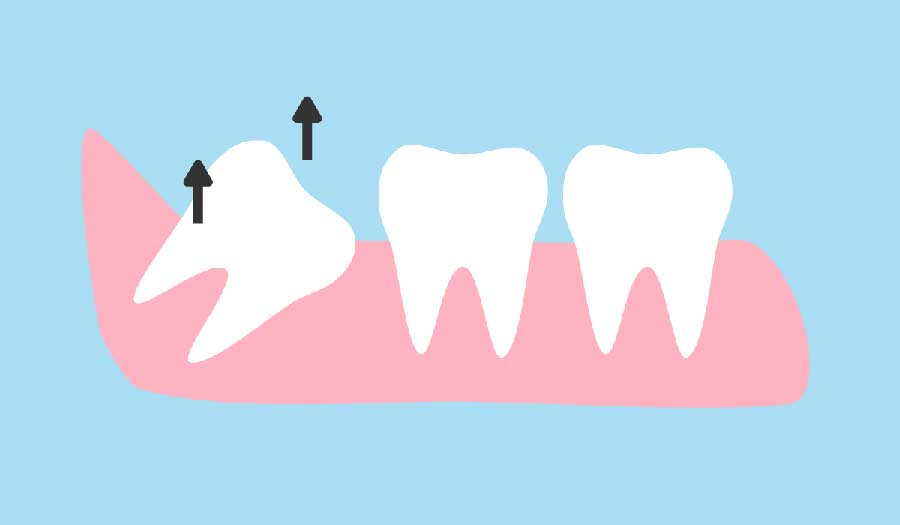

علت درد دندان عقل چیست؟

دندان عقل یا سومین دندان آسیا، عقب ترین دندان در هر یک چهارم فک انسان می باشد. این دندان معمولا در سنین 17 تا 19 سالگی می روید. اکثر بزرگسالان 4 تا دندان عقل دارند ولی برخی هم ممکن است دندان های کمتری داشته باشند.

كشيدن دندان عقل چه عوارضی دارد؟

آیا دندان عقل خود را کشیده اید؟ آیا می خواهید دندان عقل را بکشید اما نمی دانید کار درستی است یا نه؟ در بیشتر موارد کشیدن دندان عقل هیچگونه مشکلی پیش نمی آورد و باید کشیده شود. اما در بعضی مواقع ممکن است کشیدن دندان عقل با عوارضی همراه باشد. در این مطلب عوارض ناشي از كشيدن دندان عقل را با هم بخوانیم.

بهترین زمان کشیدن دندان عقل

آیا باید دندان عقلی را که به شما دردی تحمیل نمی کند، کشید؟ دندان های عقلی که باعث بروز شکایتی نمی شوند، اغلب برای جلوگیری از ایجاد مسائلی در آینده کشیده می شوند. با این حال، در صورت کشیدن دندان عقل، عوارضی مانند عفونت زخم و آسیب عصبی ممکن است ایجاد گردد.